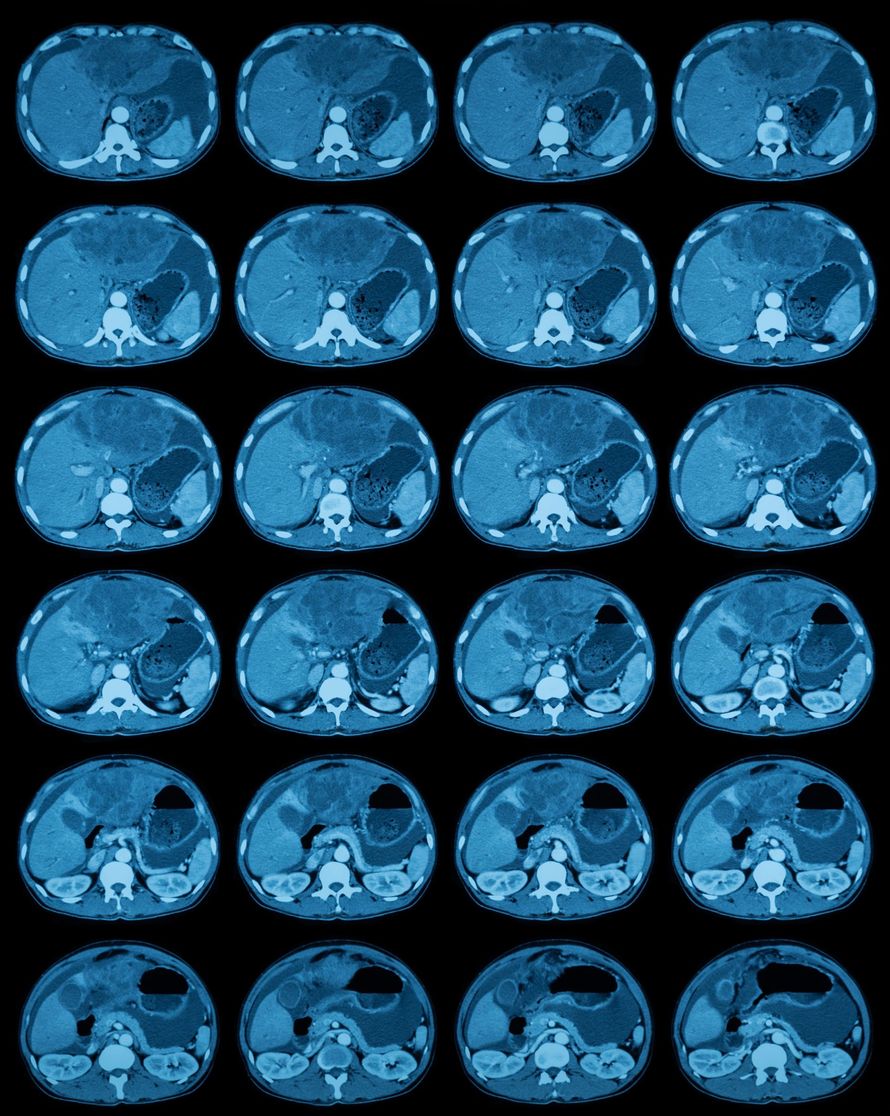

We use advanced CT technology to detect silent conditions early and give you a clearer look at your internal health. Our services include:

Full Body Scan

LEARN MOREThis scan evaluates major organs in the chest, abdomen, and pelvis. Many dangerous conditions grow silently for years. Early detection helps find tumors, cysts, stones, and structural changes early.